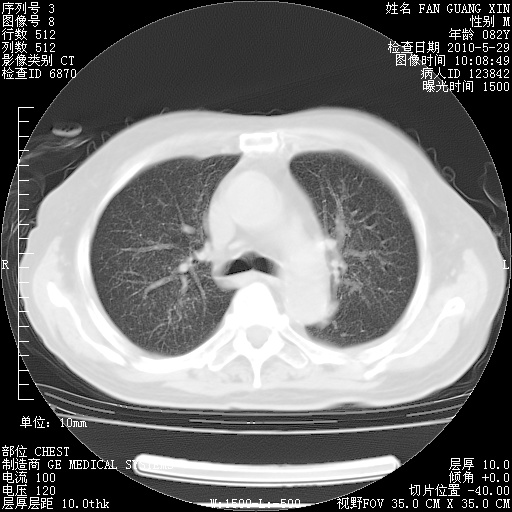

再治疗10天后的肺部CT